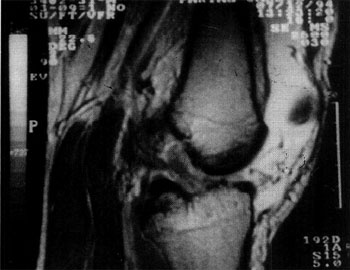

Fig. 8: Lesión Tipo III, secuencia T2.

Fig. 9: Lesión Tipo III, secuencia D.P.

TIPO III O SEVERA:

Al igual que el tipo II, esta alterada la estructura y los bordes, con idénticas características de señal para los casos agudos y crónicos. La observamos tanto en el tercio medio como proximal, involucra mas de la mitad posterior del ligamento o bien la alteración se ubica en el sector anterior. Habitualmente muestra cierta laxitud pero conserva la dirección de las fibras hacia su inserción condflea.